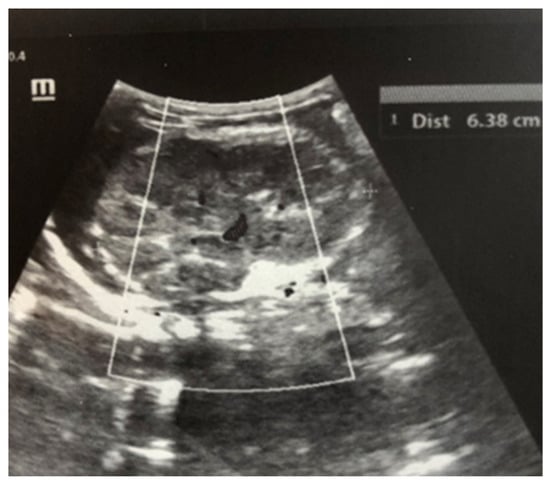

Complex therapy was performed—mechanical ventilation, antibiotics in doses adjusted according to creatinine clearance, anticonvulsants, low-molecular-weight herapin (Enoxaparin), inotropic (Dopamine), and phototherapy. The child’s condition gradually improved and he was extubated on the 9th day of the stay in the NICU. An uncomplicated post-extubation period followed. In the following 2–3 days, macroscopic hematuria was observed. On the second day after extubation, the child’s diuresis was good. The condition of the right kidney was monitored by ultrasound on the 3rd day (Figure 3), the 10th day (recovery of renal venous blood flow was observed), and at the end of the first month. On the 10th day, a decrease in kidney size was noted, and at the end of the first month, the size was below the norm for the age—i.e., the onset of renal atrophy. Follow-up examinations at 6 months and 1 year showed evidence of the atrophying of the right kidney with a longitudinal size of 2 cm, the occurrence of compensatory hypertrophy of the left kidney, normal blood pressure, and preserved renal function (Figure 4).

Although renal blood flow was restored by the 10th day, progressive atrophy of the affected kidney gradually occurred in the case presented (Figure 4). According to a study by Winyard et al. involving 23 children with neonatal thrombosis over a 15-year period [12], the length of the affected kidney exceeding 6 cm (as in our case) is typically associated with the development of renal atrophy, regardless of the treatment administered.

Figure 4. Right kidney image at 1 year of age—reduced in size, with a longitudinal size of 2.6 cm, increased echogenicity of the parenchyma, and the presence of a small subcortical cyst.